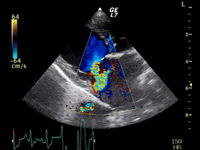

C:超音波画像 肺動脈領域の異常血流

D:左心系の拡張による二次的僧帽弁逆流

左側胸壁よりLevine 4/6の連続性心雑音が聴取された。胸部レントゲン検査において心拡大が認められ、超音波検査においても肺動脈領域に連続的な異常血流が観察された。大学病院を紹介受診され、手術が行われた。現在はACE阻害薬のみの内服で補助的治療を行っている。